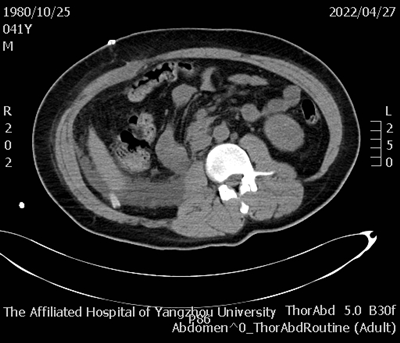

据悉,患者因“下腹部胀痛2天加重6小时”于西区医院外科急诊就医,经全腹部CT检查提示:右侧腹膜后巨大占位并破裂、出血,不除外肾脏或肾肿瘤破裂。据此情况,外科急诊遂收治泌尿外科进行救治。

术前腹部增强CT_副本.png